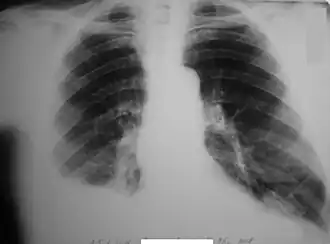

![]() Закрытые переломы VI, VII, VIII, IX рёбер справа. Правосторонний гемоторакс | |